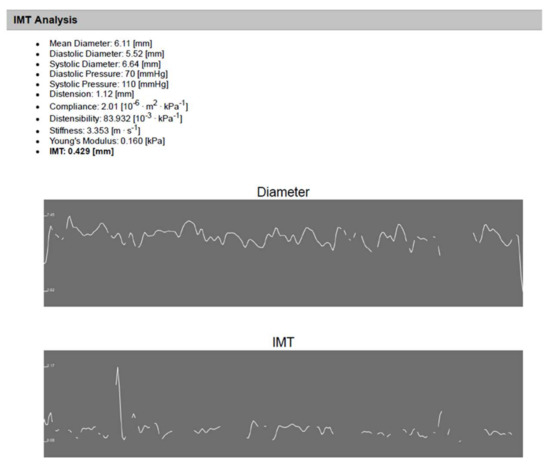

Echo-Tracking

| CIMT (mm) | A versus B A versus C A versus D B versus D C versus D B versus C | 0.0001 0.3 0.0001 0.4 0.04 0.01 | ||||

| Mean ± SD | 0.46 ± 0.03 | 0.36 ± 0.08 | 0.43 ± 0.1 | 0.38 ± 0.08 | ||